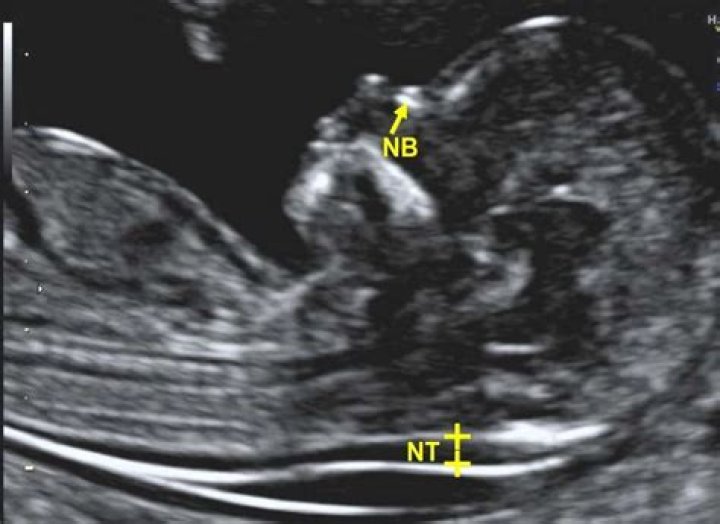

Can neurofibromatosis be detected before birth?

How Is Neurofibromatosis Type 1 Diagnosed? NF1 may be diagnosed before or at birth using genetic (DNA) tests. A doctor usually suggests genetic testing for NF1 if: a parent or sibling of an unborn baby is known to have NF1.